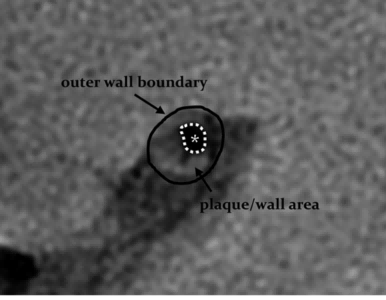

埃斯科核心实验室(IsCore image corelab) 是晓得(北京)商业发展有限公司旗下 的独立第三方核心实验室。由经验丰富的临床专家团队和影像放射专家团队组成, 致力于帮助临床医生和医疗领域的公司进行细致的、标准的、规范的影像管理和 判读。IsCore 影像实验室提供的影像判读数据已经为多家医疗机构的科研课题提 供数据支持,同时也已经协助国内外数个产品研发上市提供科学帮助。我们实验室的影像评价者均在国内顶尖专科医院接受过临床影像专业的系统学 习与规范培训,有多年的临床工作经验,以及强大的技术支持,能准确判读 MRI, HRMRI, DSA, OCT, CFD, VU 等影像,给出标准规范的报告结果,最低限度减少 了人为因素对试验结果的影响有助于科研成果产出和产品研发。